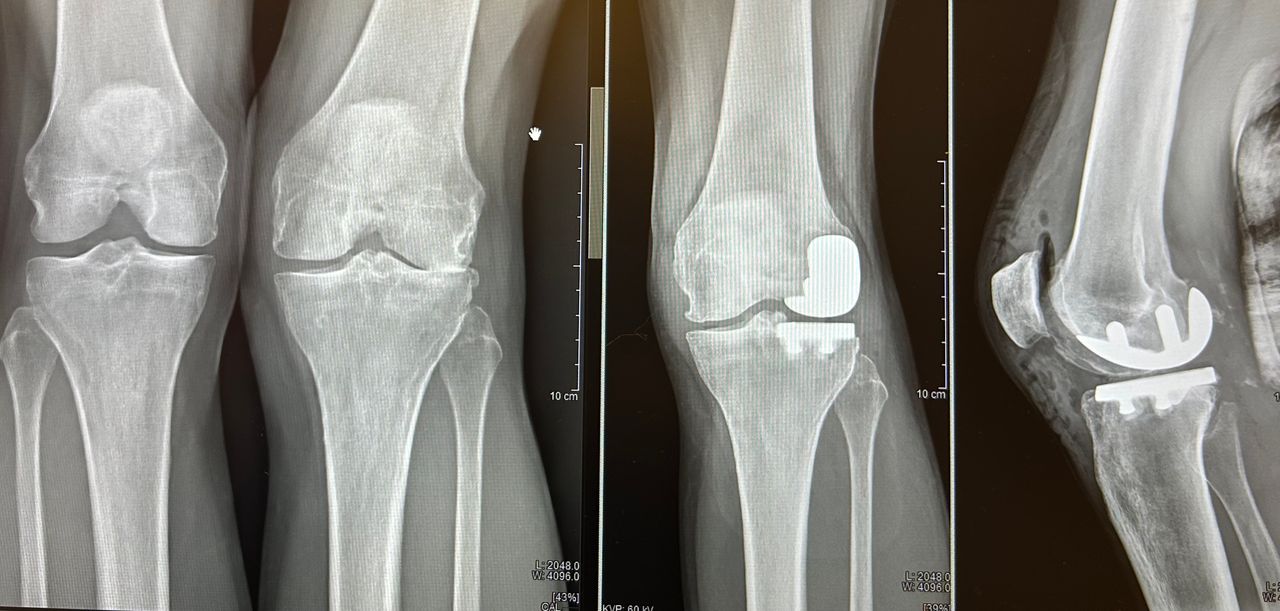

Mi chiamo Luca Luciano e sono un medico ortopedico specializzato nella chirurgia protesica dell’anca e del ginocchio. Da anni mi occupo del trattamento dell’artrosi severa, utilizzando tecniche mini invasive moderne che mi permettono di ridurre il dolore post-operatorio e favorire un recupero più rapido e sereno.

Credo in una chirurgia precisa, attenta e rispettosa dei tessuti. Ogni intervento viene pianificato con cura, valutando la storia clinica, le esigenze e lo stile di vita della persona che ho di fronte. Il mio obiettivo non è solo sostituire un’articolazione consumata, ma restituire qualità di vita, autonomia e sicurezza nei movimenti quotidiani.

• Chirurgia del ginocchio